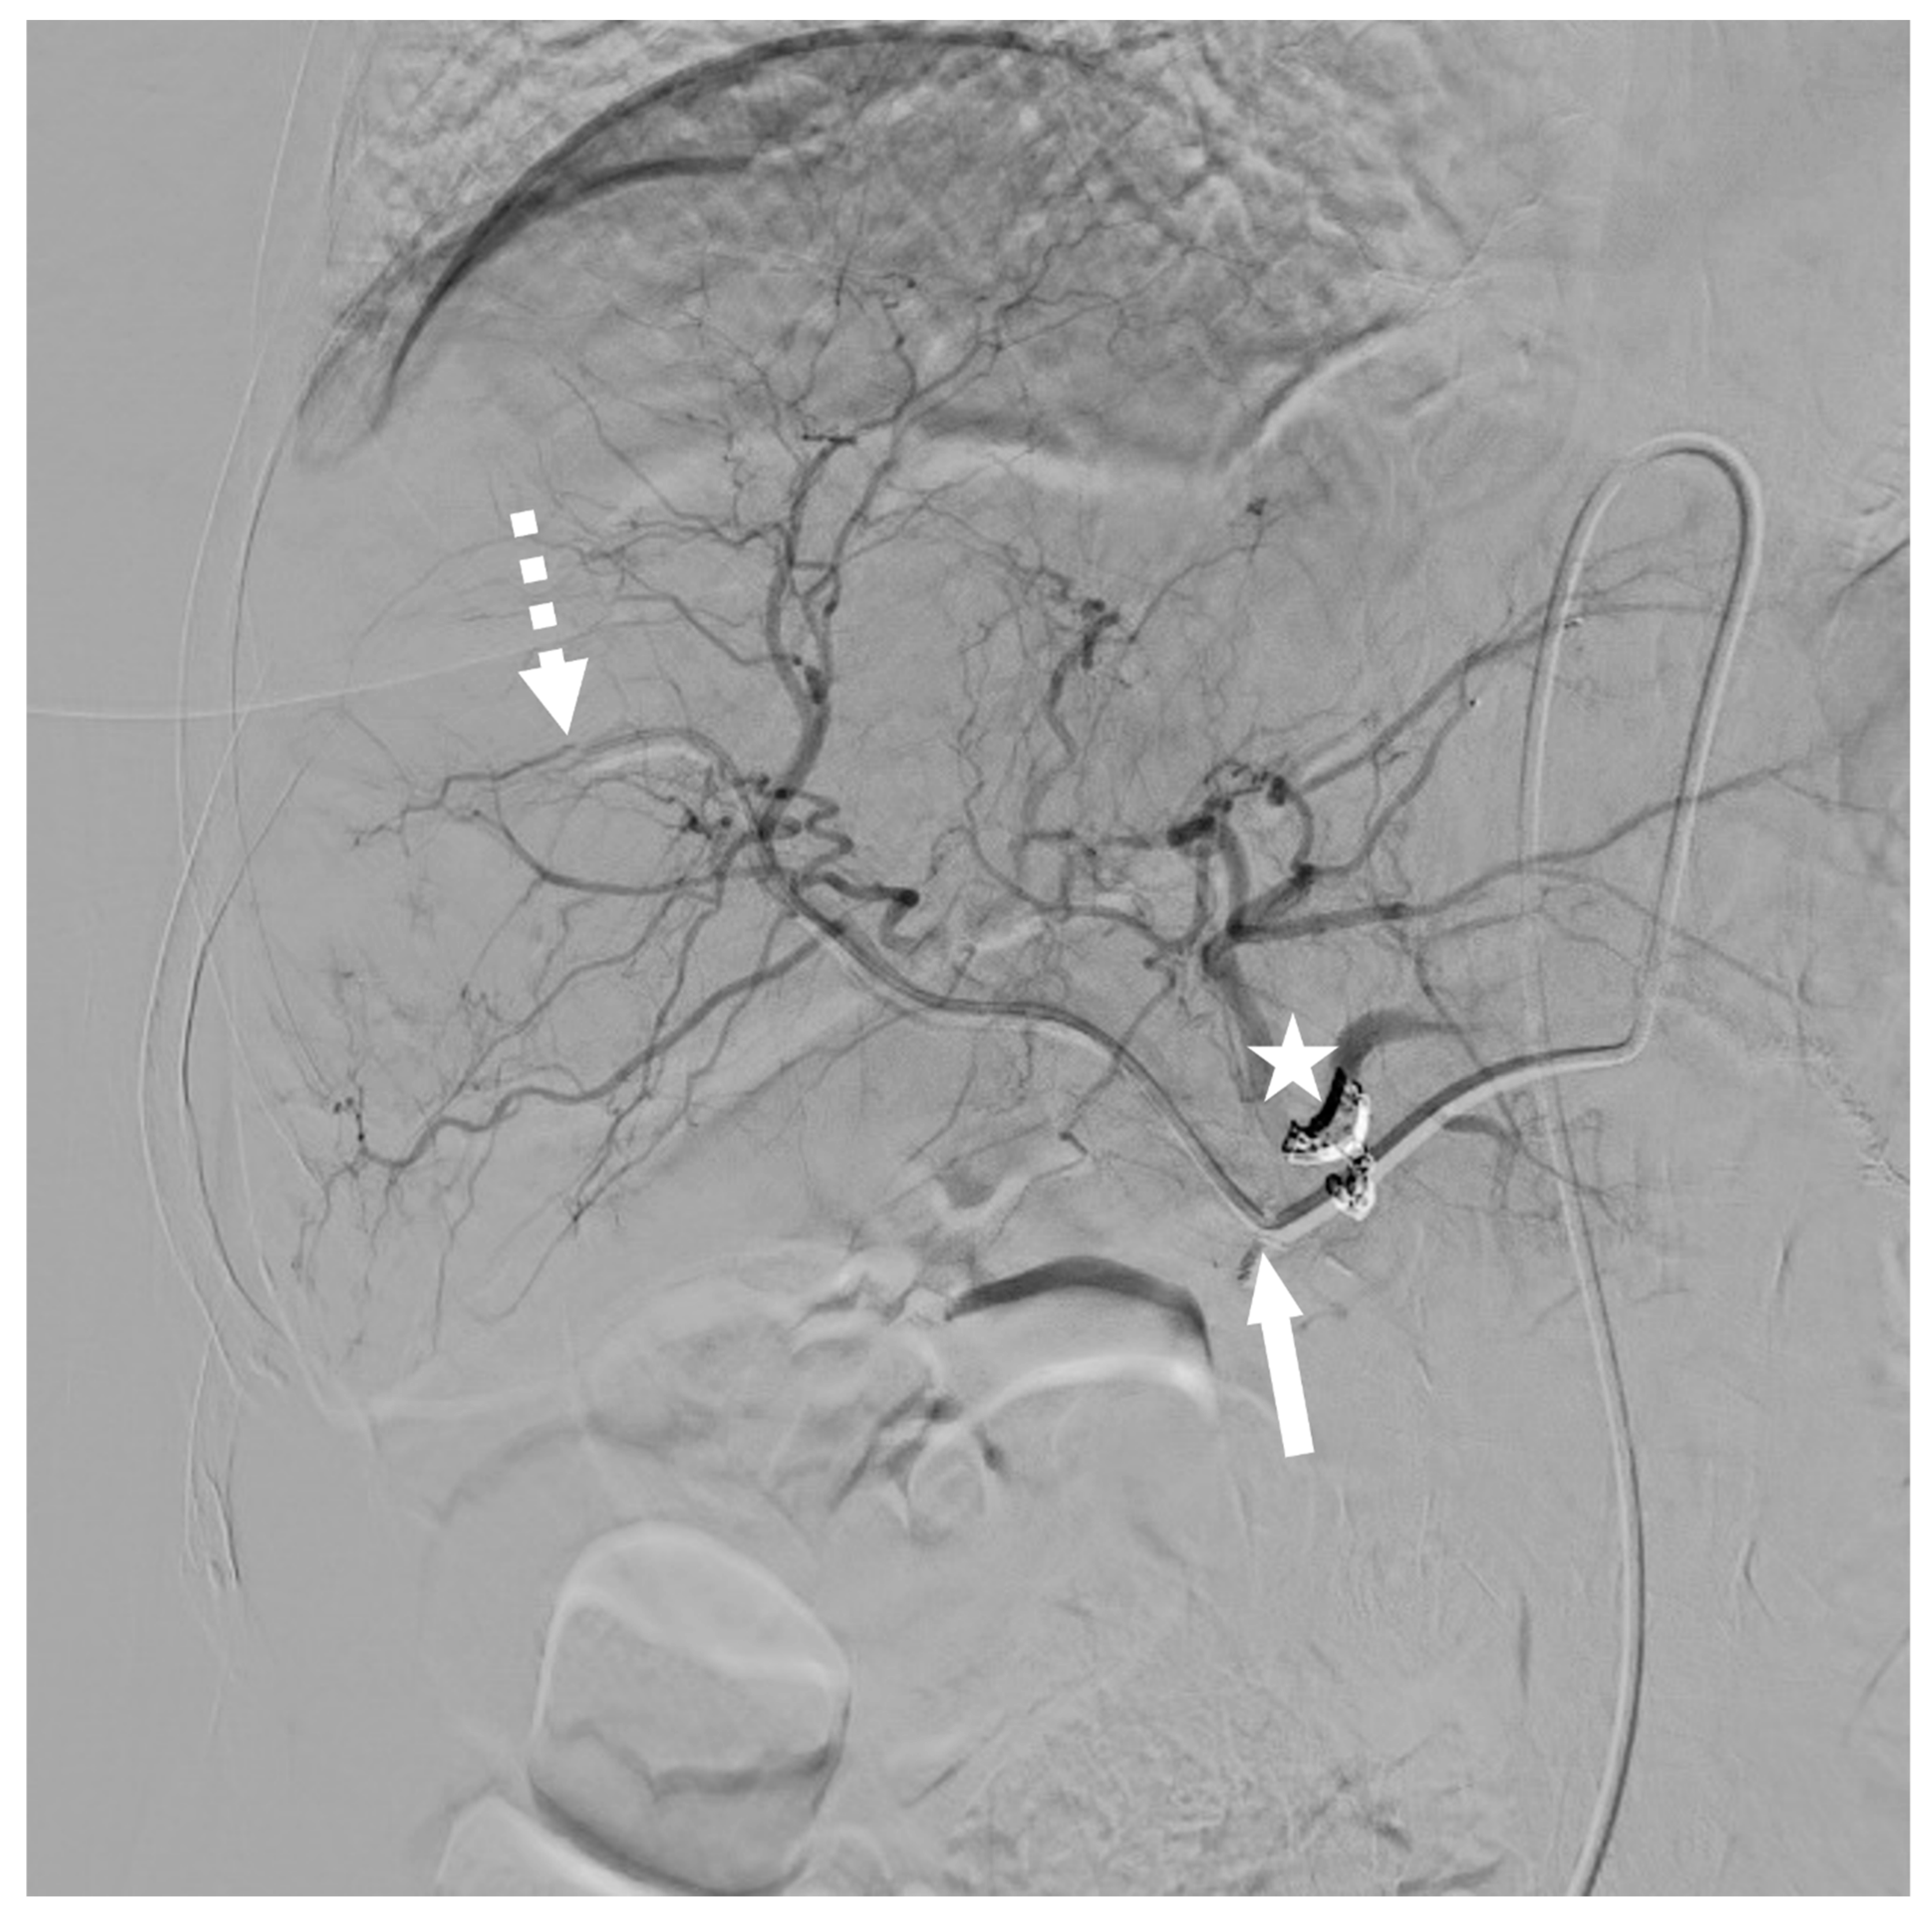

3.2. Modified Implantation Technique

3.3. Technical Outcomes